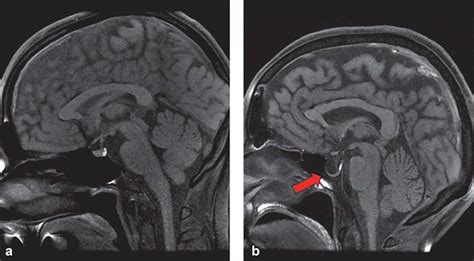

Web empty sella syndrome (ess), also known as arachnoidocele, is a radiologic finding in which the sella turcica appears empty due to cerebral spinal fluid (csf). Web partial empty sella is suggestive that some of the pituitary gland is visible on the mri scan. It’s treatable with hormone medications and sometimes surgery. Web empty sella syndrome affects the pituitary gland but may not cause symptoms. The sella turcica is an indentation in the sphenoid bone at the. It is of two types, primary and secondary. Having an empty sella show up on your brain. Learn more about the condition, including symptoms, diagnosis, and treatment. Web empty sella syndrome is a rare disorder related to a part of the skull called the sella turcica.

Web empty sella syndrome affects the pituitary gland but may not cause symptoms. Web partial empty sella is suggestive that some of the pituitary gland is visible on the mri scan. It is of two types, primary and secondary. The sella turcica is an indentation in the sphenoid bone at the. Web empty sella syndrome (ess), also known as arachnoidocele, is a radiologic finding in which the sella turcica appears empty due to cerebral spinal fluid (csf). It’s treatable with hormone medications and sometimes surgery. Learn more about the condition, including symptoms, diagnosis, and treatment. Web empty sella syndrome is a rare disorder related to a part of the skull called the sella turcica. Having an empty sella show up on your brain. Web empty sella syndrome affects the pituitary gland but may not cause symptoms.